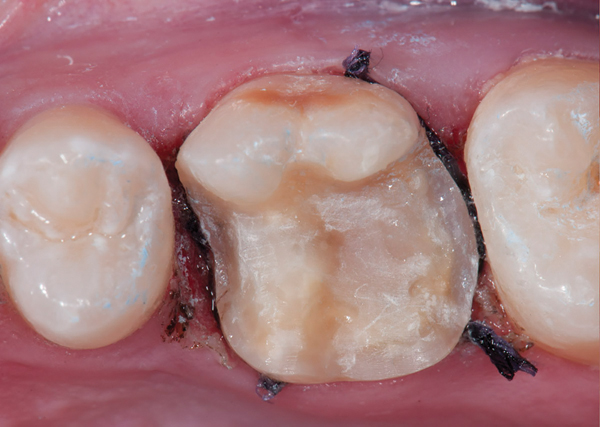

Fig 9. Preoperative view (Fig 9), preparation with composite block-out restoration (Fig 10), and final cementation of CL-IIb material (Fig 11) (final ceramic contour and stain by Steve Lee, CDT, MDC).

Fig 10. Preoperative view (Fig 9), preparation with composite block-out restoration (Fig 10), and final cementation of CL-IIb material (Fig 11) (final ceramic contour and stain by Steve Lee, CDT, MDC).

Fig 11. Preoperative view (Fig 9), preparation with composite block-out restoration (Fig 10), and final cementation of CL-IIb material (Fig 11) (final ceramic contour and stain by Steve Lee, CDT, MDC).